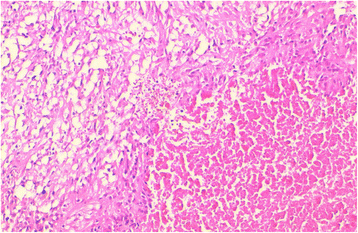

The histological view of a GIST tumor with prominent necrosis (HES × 200)